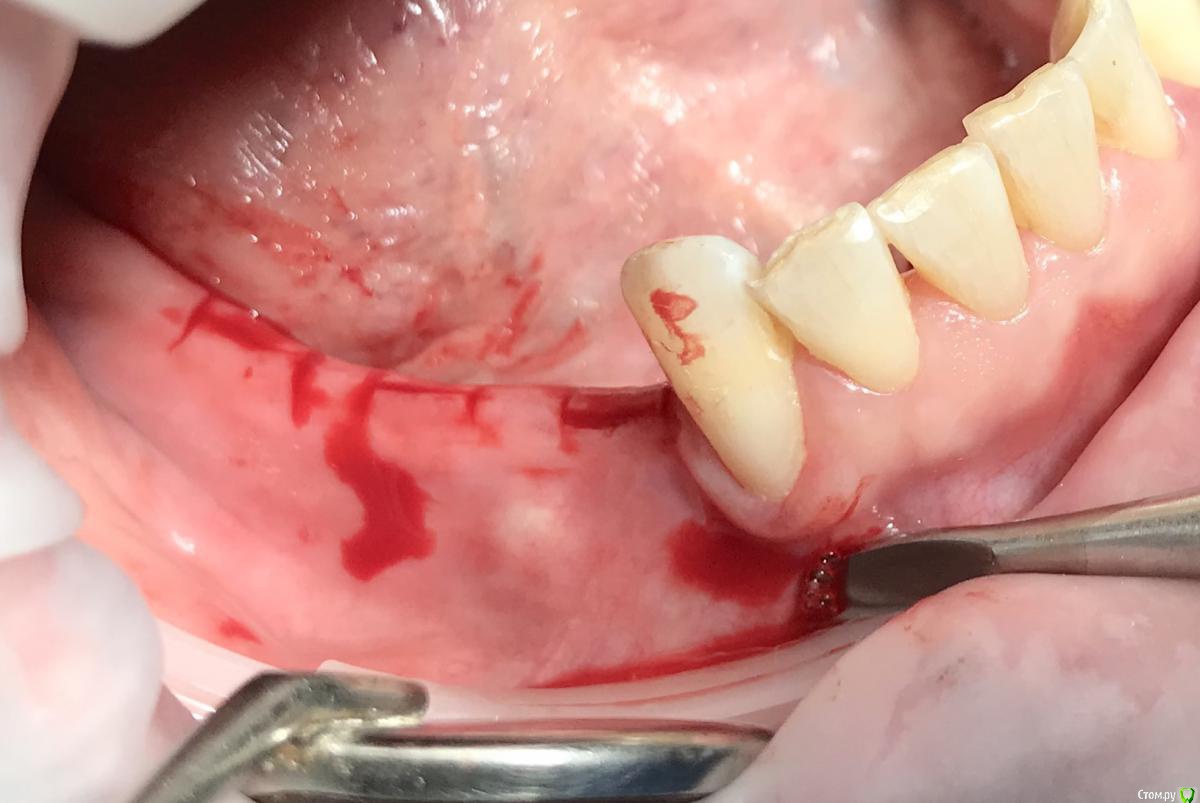

колесников Опубликовано 25 ноября, 2018 Поделиться Опубликовано 25 ноября, 2018 Фото для примера,из разряда было-стало. Обычно рядовые случаи не фотографирую,но тут решил запечатлеть. Тоннель плюс имплантация,делал впервые. Примерно понятно как узкий гребень превращается в широкую сосиску. 2 Ссылка на комментарий

колесников Опубликовано 26 ноября, 2018 Поделиться Опубликовано 26 ноября, 2018 Скажите плз, импланты одномоментно с графтингом, если да , то какой шаблон, по КТ?Да,тут одномоментно. Хорошо это или нет,будет ли все удачно-не могу сказать,делал так впервые,главное понять как это работает.Делать отсроченно мне уже скучно. Повторять не рекомендую. Шаблон не использовал,он тут не поможет,гребень 2мм. Ссылка на комментарий

колесников Опубликовано 26 ноября, 2018 Поделиться Опубликовано 26 ноября, 2018 Скальпель 15С,пинцет ,серповидная гладилка,викрил. Учусь у всех по немногу. Лучший учитель опыт. 1 Ссылка на комментарий